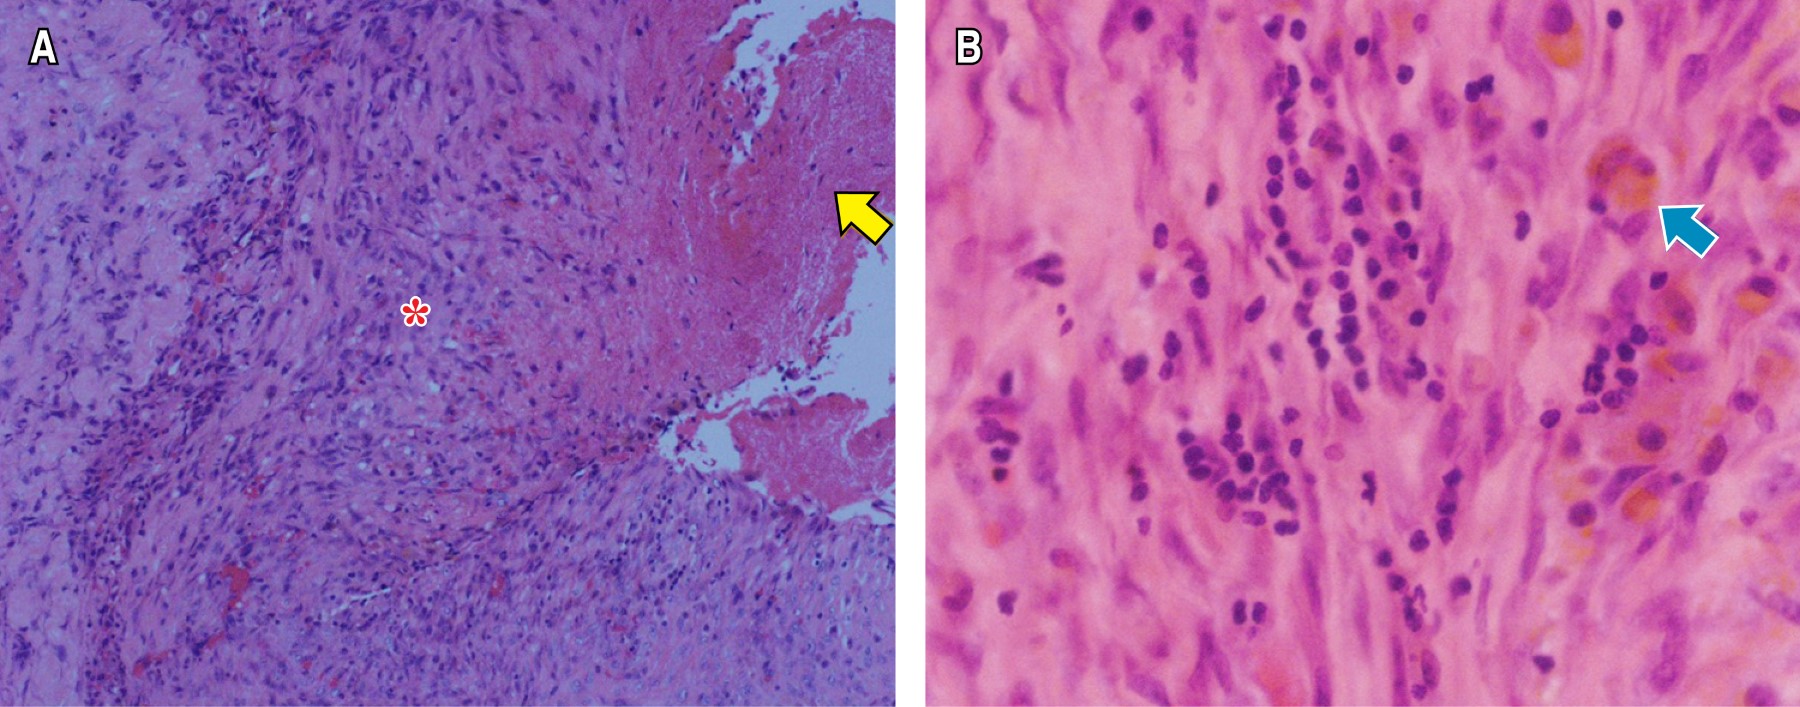

La angio-TC de tórax fue negativa para TEP, con evidencia de OVE del lado derecho y neumotórax contralateral que colapsaba 90% del pulmón (Figura 2A), por lo que se realizó una toracostomía cerrada izquierda de urgencia, sin lograrse la expansión pulmonar. Al tercer día de estancia hospitalaria, presentó deterioro de la oxigenación que requirió inicio de suplencia de oxígeno por cánula de alto flujo e ingresó a la unidad de cuidados intensivos (UCI) sin requerimiento de VM. La TC de alta resolución control (Figuras 2By C) demostró OVE, áreas de crazy paving de predomino derecho, neumotórax apical derecho pequeño (< 10%), neumomediastino y enfisema de los tejidos blandos del hemitórax izquierdo. Fue llevado a una segunda toracostomía cerrada a nivel apical izquierdo por cirugía de tórax, con persistencia del colapso pulmonar ipsilateral, por lo que se realizó decorticación y pleurectomía parietal por toracoscopia, con expansión satisfactoria. La patología reportó pleuritis crónica (Figura 3). Se indicó manejo conservador del neumotórax derecho, con expansión pulmonar en imágenes posteriores.

La patología del segundo caso fue similar a lo documentado por Chang et al., quienes encontraron en algunos pacientes pleuritis crónica en muestras histopatológicas de pacientes llevados a cirugía torácica por complicaciones por COVID-19.25